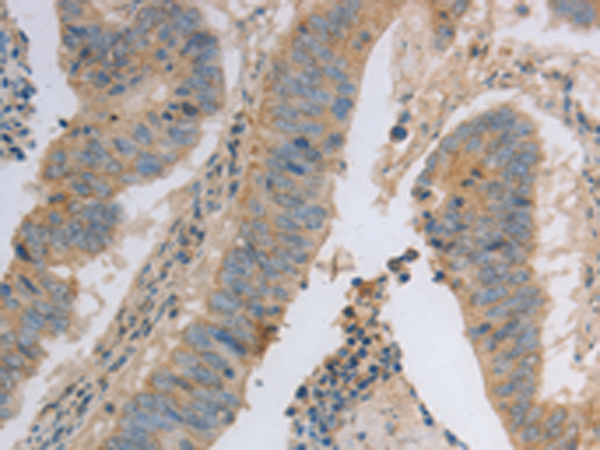

分类: 科研抗体货号: P07433别名: NRAGE, DLXIN-1应用: WB,IHC反应种属: Human, Mouse, Rat